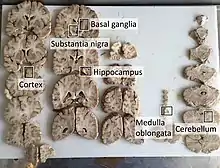

The body block that was used earlier to elevate the chest cavity is now used to elevate the head. To examine the brain, an incision is made from behind one ear, over the crown of the head, to a point behind the other ear. When the autopsy is completed, the incision can be neatly sewn up and is not noticed when the head is resting on a pillow in an open casket funeral. The scalp is pulled away from the skull in two flaps with the front flap going over the face and the rear flap over the back of the neck. The skull is then cut with a circular (or semicircular) bladed reciprocating saw to create a "cap" that can be pulled off, exposing the brain. The brain is then observed in situ. Then the brain's connections to the cranial nerves and spinal cord are severed, and the brain is lifted out of the skull for further examination. If the brain needs to be preserved before being inspected, it is contained in a large container of formalin (15 percent solution of formaldehyde gas in buffered water) for at least two, but preferably four weeks. This not only preserves the brain, but also makes it firmer, allowing easier handling without corrupting the tissue.